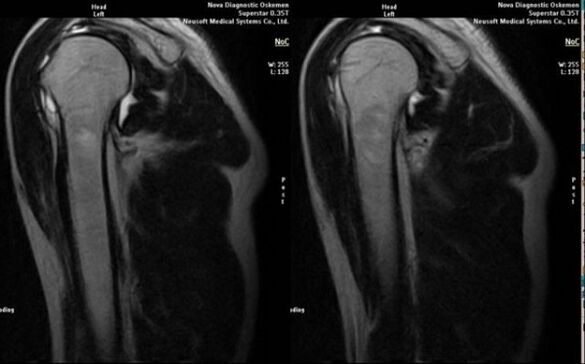

• magnetic resonance and computed tomography;

The direct development of arthrosis is a significant narrowing of the joint space, sclerosis of subcartilaginous structures, thinning of the chondrocyte layer itself, the appearance of osteophytes and the appearance of salt crystals and the appearance of salt crystals and the appearance of salt crystals and the appearance of salt crystals and the appearance of salt crystals and the appearance of salt crystals.